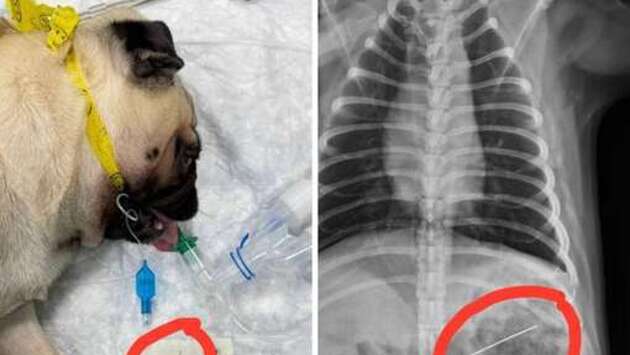

В Липецке собака проглотила иголку с ниткой и оказалась на операционном столе. Об этом сообщает Telegram-канал "Липецк с огоньком". Инцидент произошел с мопсом по кличке Джамбо. Во время игры пес проглотил иголку, после чего хозяева сразу отвезли животное в ветеринарную клинику. Хирурги клиники провели собаке операцию. Они смогли вытащить иголку из организма мопса с помощью эндоскопа. До этого россиянам рассказали, как помочь проглотившему инородный предмет питомцу. Ветеринар особо отметил, что с кошками и собаками нельзя играть, используя мелкие предметы, которые они могут съесть. Также нельзя оставлять вещи, которые могут заинтересовать питомца, без присмотра.